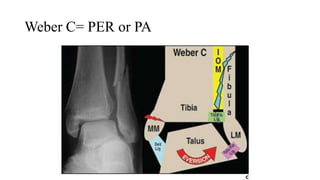

Weber C= PER or PA

PER ( sấp- xoay ngoài)

• PER1: Gãy ngang mắt cá trong or

đứt dây chằng bên trong

• PER2: Đứt d.c syndesmosis trước

• PER3:  rách màng interosseous (

màng liên cốt) lan lên trên gây

gãy xương mác trên cao

• PER4: Vỡ mắt cá sau

PA ( Sấp- Khép)

• PA1: Gãy ngang mắt cá trong ( dưới

syndesmosis) hoặc đứt dây chằng denta

• PA2: Đứt dây chằng chày mác trước

• PA3: Gãy mắt cá ngoài( gãy chéo )